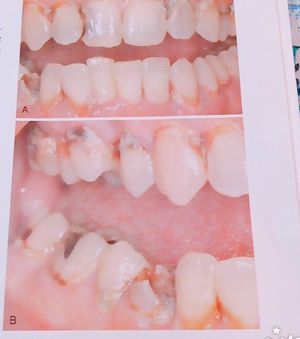

Acutr,Rampant caries in both anterior and posterior teeth

Acute

Dentalcaries

Rampant